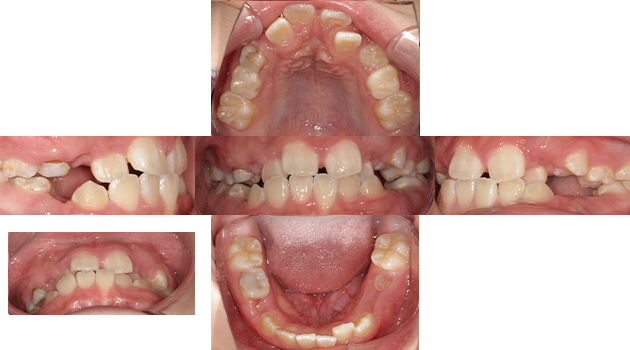

小児矯正と成人矯正

主訴 歯並びを綺麗にしたい。

治療期間 3年

治療費 矯正代金770,000円(税込)

治療内容 小児矯正と成人矯正を行ない健康的な歯並びを手に入れることができた。